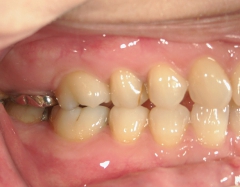

矯正歯科 治療前